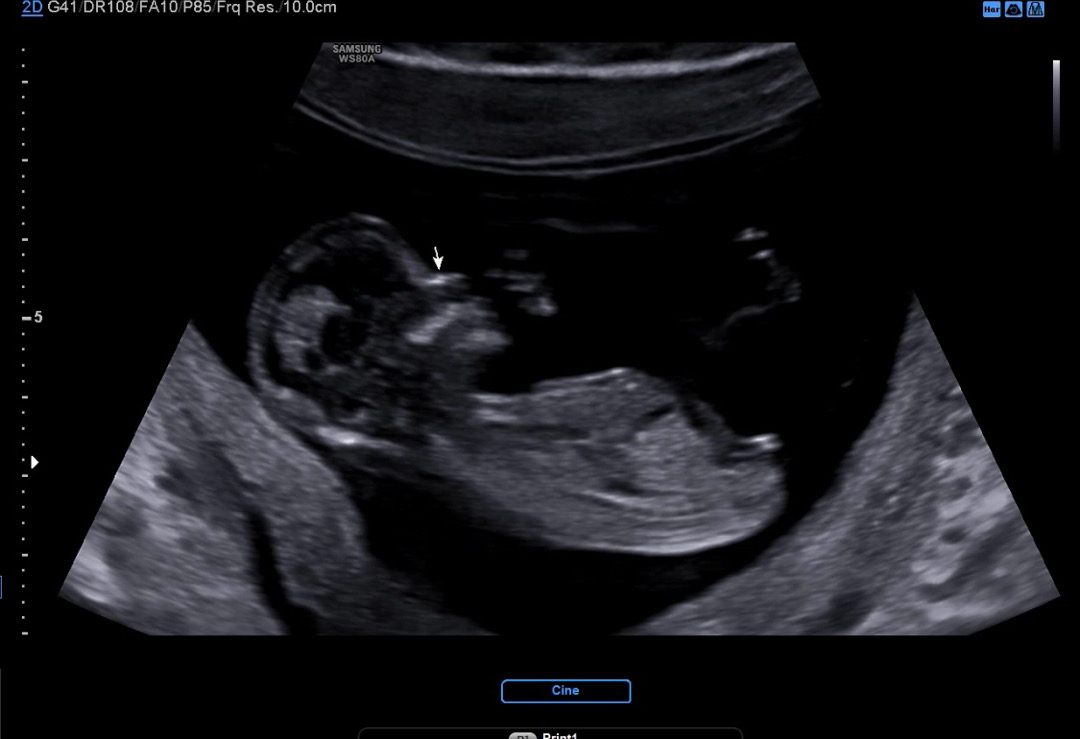

13주 0일 각도법 문의드려요!

안녕하세요~13주 0일 되는 기쁨이맘입니다! 오늘 1차 기형아 검사하고 왔는데 딸인지 아들인지 너무 궁금하네요^^ 점심을 먹고 검사하러 가서 그런지 기쁨이가 점프도 수시로 하고 다리도 꼬았다 펼쳤다 아주 활발히 놀고 있더라구요ㅎㅎ 고수님들 저도 성별 부탁드립니다!🧡